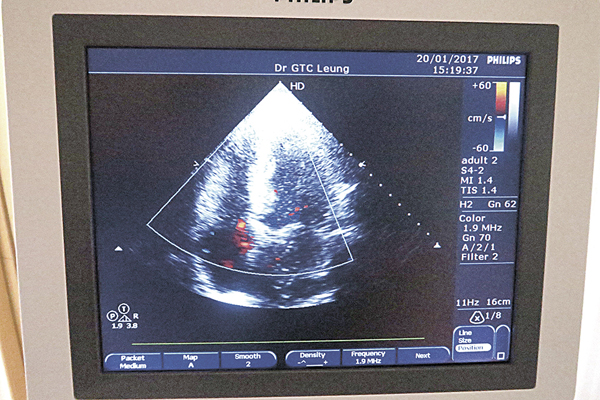

梁醫生表示,常見的確診工具是心臟超聲波檢查,能發現心臟泵血功能是否正常,只是舒張性心臟衰竭較收縮性心臟衰竭難發現,若同時發現心肌增厚,便有需要再進行運動超聲波檢查以確定是哪種心臟衰竭問題。確診後,患者亦需定期覆診,以追蹤及監測射頻指數,即每次心跳期間由心臟輸出的血液百分比,以判斷心臟輸送血液的功能運作情況。